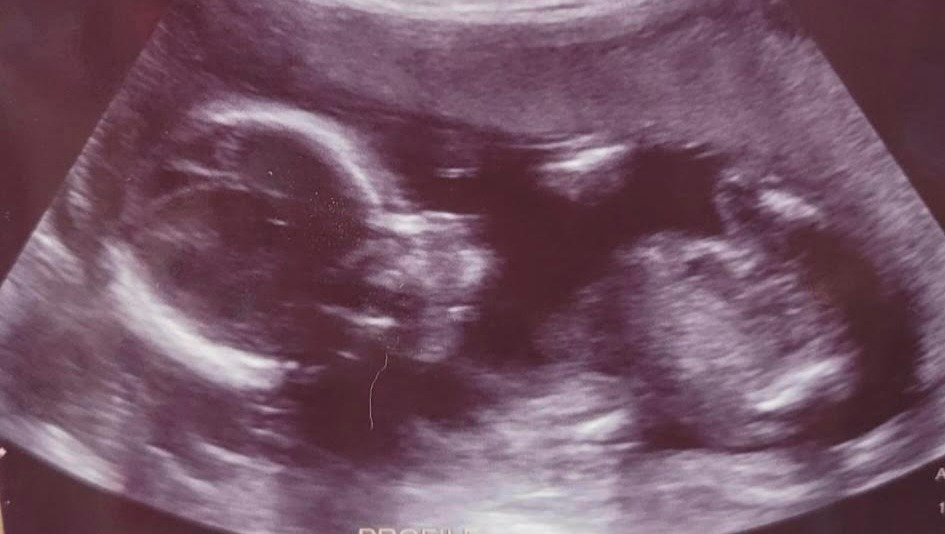

At 29 weeks pregnant, Stephanie and baby Ash were emergency airlifted to the University of Washington Medical Center in Seattle, WA. Stephanie has been experiencing bleeding since the 25 week mark due to the baby's placenta partially detaching (placenta abruption). In addition to that, she has been having premature labor contractions that negatively impact Ash's vitals like heart rate, etc. Stephanie's pregnancy is considered high risk and she is being monitored indefinitely until delivery at UW in the antepartum unit. We are thankful for every single day that she and Ash push through this. The good news is- mama and baby are in such good hands at the University of Washington, which is ranked the top hospital in the state.